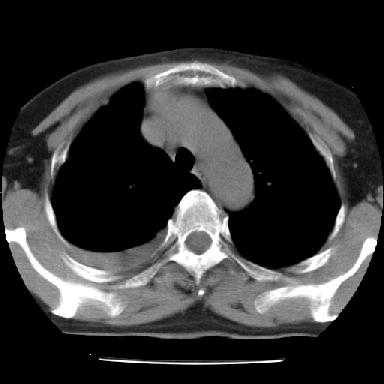

以下是引用苯小孩在2007-4-13 16:20:00的发言:[br]1、右下肺中央型肺癌并阻塞性肺不张、肺内转移、胸椎右侧附件亦有转移<横断层面第8层>.[br]2、右侧胸腔积液.

以下是引用swyyy2007在2007-4-13 15:31:00的发言:[br]右肺门下区肿块,右肺下叶支气管阻塞,右肺下叶不张,右侧大量胸腔积液,右肺中叶见结节状高密度影,边缘清,纵隔内见肿大淋巴结。首先考虑右下肺中心型肺癌伴右肺下叶不张、中叶、纵隔淋巴结转移。右侧胸腔积液。